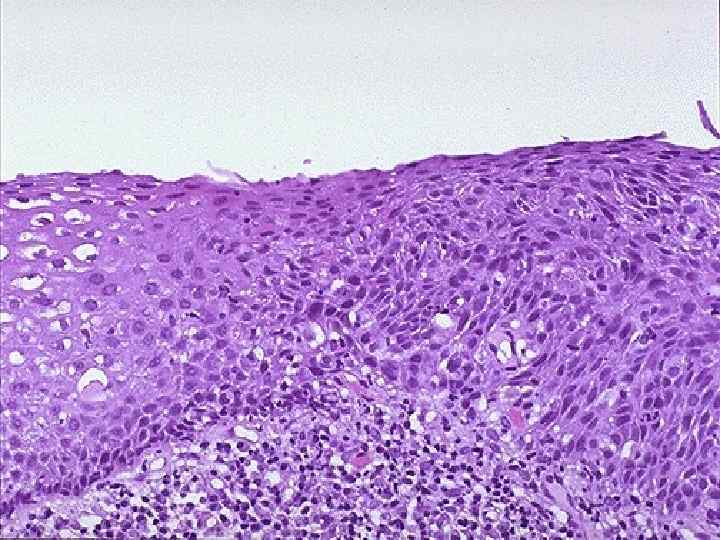

Рак шейки матки n Рост – экзофитный Гистологически – плоскоклеточный рак n